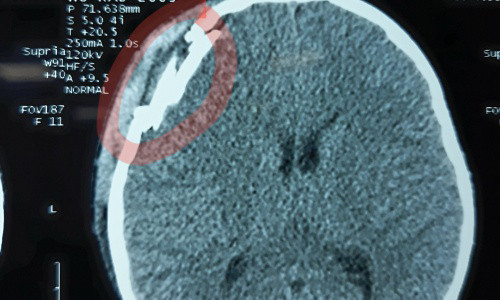

Hình ảnh chụp CT cho thấy trẻ bị vỡ xương sọ.

Cú đập mạnh khiến bé ngất xỉu, được người nhà đưa vào Bệnh viện Hữu nghị Việt Nam - Cu Ba Đồng Hới cấp cứu. Bé bị đau đầu, chóng mặt, buồn nôn, chảy máu mũi. Kết quả chụp phim CT scanner sọ não cho thấy bé bị chấn thương sọ não, vỡ xương sọ vùng trán phải, tụ máu ngoài màng cứng.